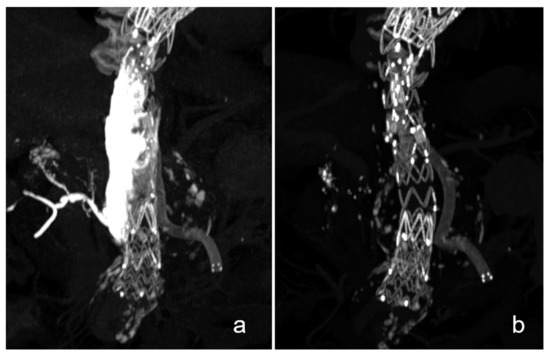

3.2. Case Descriptions